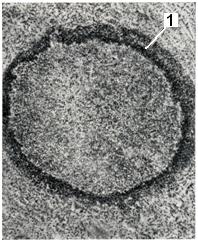

Стенки абсцесса в ранней стадии его формирования покрыты гнойно-фибринозными наложениями и обрывками некротизированных тканей. В дальнейшем по периферии абсцесса развивается зона демаркационного воспаления, составляющий ее инфильтрат служит основой для формирования пиогенной мембраны, образующей стенку полости (рис. 1). Пиогенная мембрана представляет собой богатый сосудами слой грануляционной ткани. Постепенно в той ее части, которая обращена в сторону окружающих абсцесса тканей, происходит созревание грануляций. Таким образом, если абсцесс приобретает хроническое течение, в пиогенной мембране образуются два слоя: внутренний, обращенный в полость и состоящий из грануляций, и наружный, образованный зрелой соединительной тканью (рис. 2).